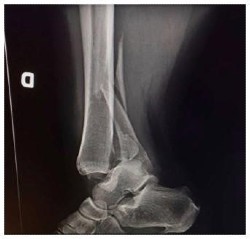

Fracture comminutive du tibia-péroné (radiographie de la cheville en latéral).